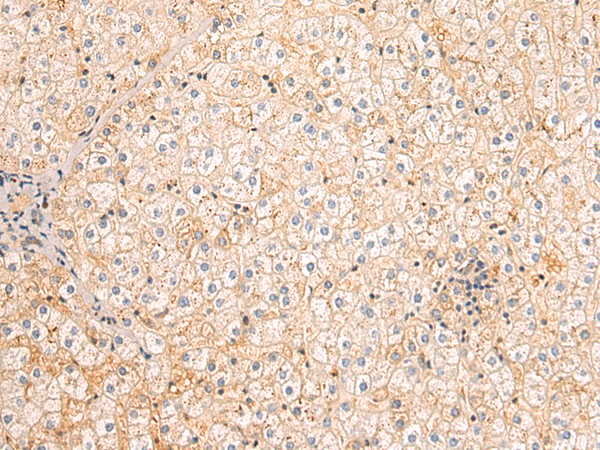

分类: 科研抗体货号: P08313别名: FAPA; SIMP; DPPIV; FAPalpha应用: WB,IHC反应种属: Human, Mouse